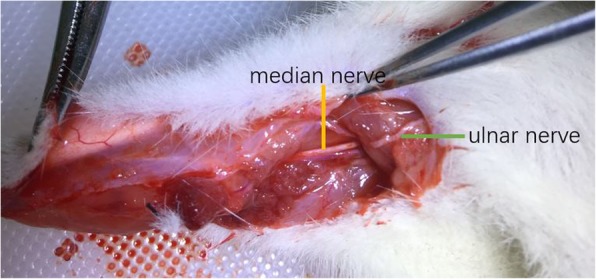

Group A (cC7 --- median nerve): A right longitudinal incision was made on the inner side of the upper arm. The ulnar and median nerves were identified near the retracing point of the ulnar nerve. (Fig. 1) Both of them were cut off. The proximal end of the ulnar nerve was sutured to the distal end of the median nerve without tension.

Fig. 1.

cC7 transfer to median nerve: The ulnar nerve and median nerve were identified at the turning point of ulnar nerve